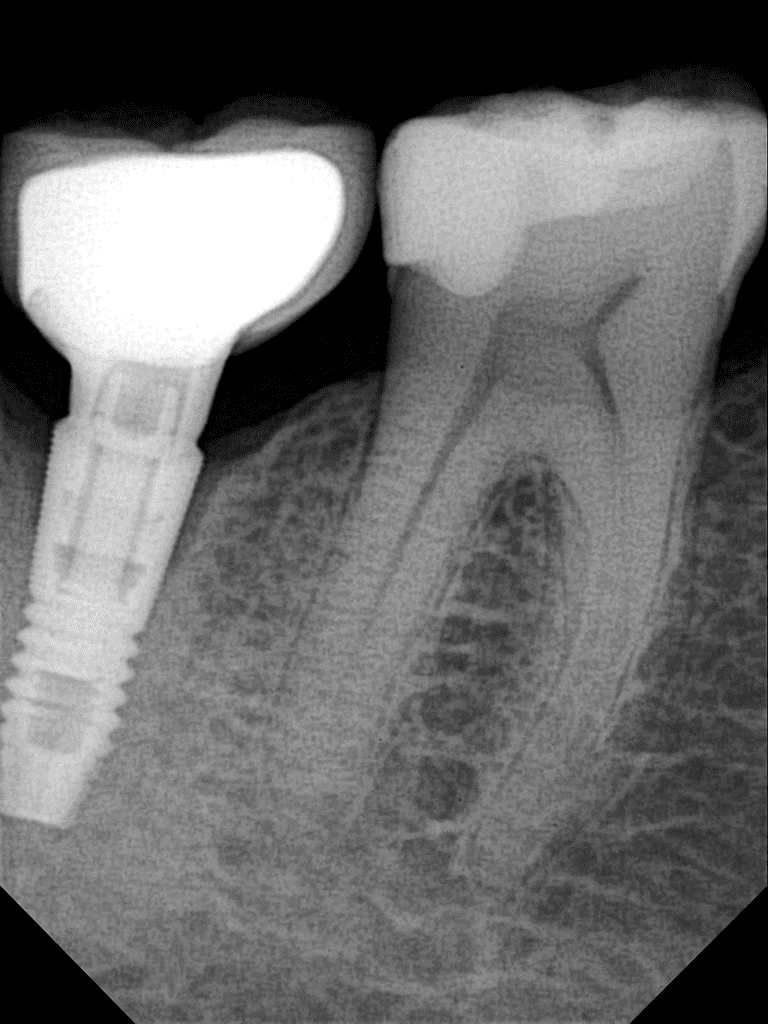

OPTEO Sensor – Klinische Bildgalerie

Ultra-HD Bildqualität – 18,5 Mikron Präzision Außergewöhnlich klare und detaillierte intraorale Bildgebung.

Unser intelligenter Scharfzeichnungsalgorithmus – speziell für die apikale Radiographie entwickelt – liefert beispiellose diagnostische Klarheit durch hochleistungsfähige Bildverarbeitung.

- Verbesserte Klarheit & Präzision für präzise Diagnostik

- Reduzierte Unschärfe & Artefakte – selbst bei komplexer Anatomie